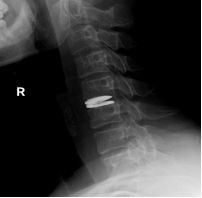

术前颈椎MRI提示颈5/6椎间盘突出明显

术后DR提示假体位置良好